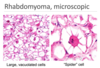

What pathology is shown in the provided image

- Rhematic Heart Disease

-

Aschoff body: small, subtle areas of necrosis- we can see the inflammatory cells responding to & causing the necrosis

- lymphocytes, plama cells, macrophages (Anitschkow cells

- Elongated cell on bottom photo are Anitschkow cells, which are specially activated, specialized macrophages (caterpillar cells)

- in cross section, look like Owl Eyes or Target

- Definitively diagnostic for Rheumatic Fever